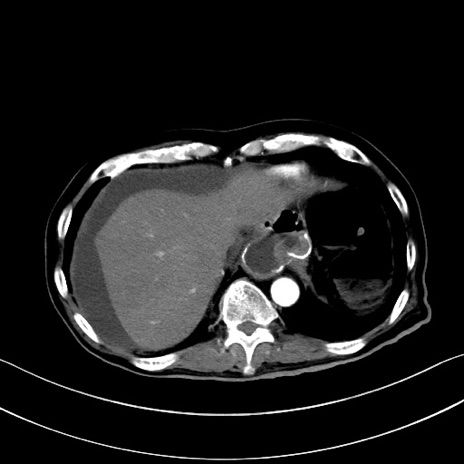

症例28(横断像)

【症例】60歳代男性

【主訴】嘔吐

【現病歴】胃癌にて胃全摘後。食思不振が悪化し、夜中に嘔吐することがある。

【既往歴】胃癌、胃全摘、脾摘、胆摘後

【データ】WBC 5900、CRP 10.56